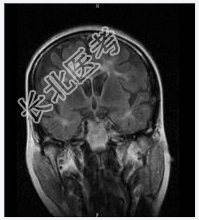

- [材料题] 患者女,28岁,反复左下肢无力4年余,痛觉减退2月余。查体:神清,左局部触觉减弱,左下肢肌力Ⅳ级,双巴氏征(+)。2001年MR示:脑脱鞘改变。行头颅MR平扫。

- 简答题1、诊断及依据是什么?

- 简答题2、鉴别诊断有哪些?